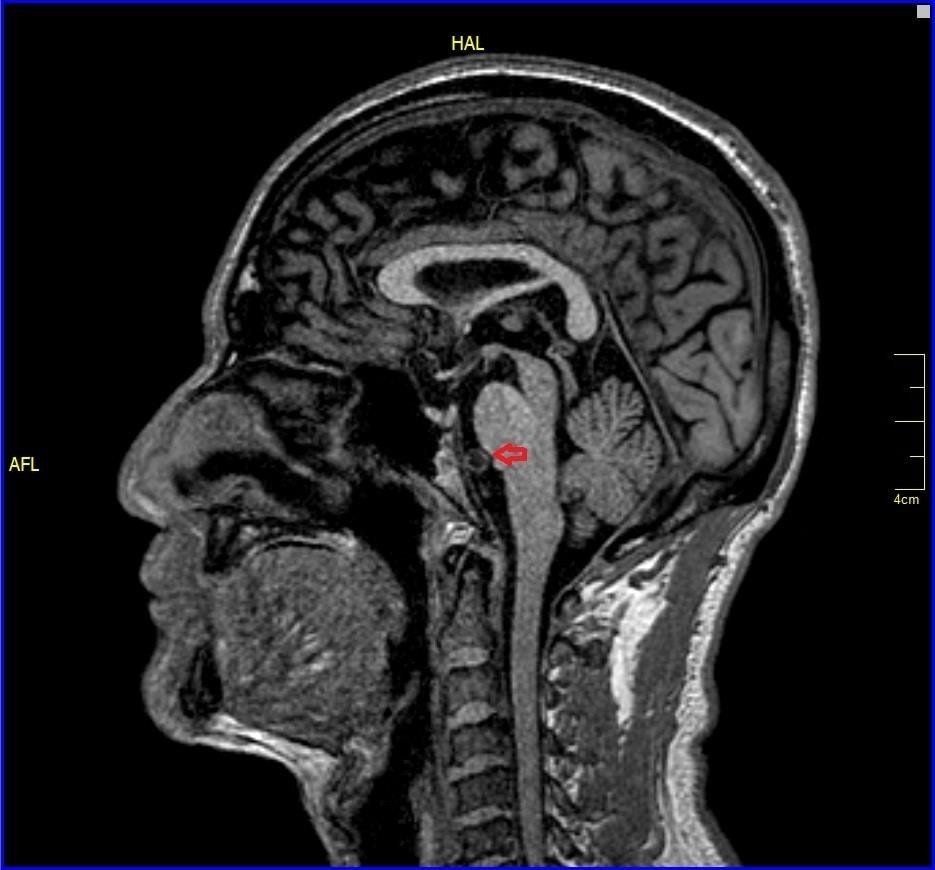

All other blood investigations including thyroid function tests and autoimmune screening were within normal limits. Plain computed tomography (CT) brain was done and revealed well-defined hypodensities seen in right lentiform nucleus chronic infarct.1 Otherwise, no intracranial haemorrhage and no acute ischemic infarcts seen at other areas. Brain magnetic resonance angiography (MRA) was ordered and it showed impingement of V4 vertebral artery to anterior lower pons near midline which is the exit of the left abducens nerve from the pons and also trigeminal nerve (blue arrow) and right abducens nerve (Figure 1-3) No abnormal signals were seen in brainstem. After ruling out other aetiologies of sixth cranial nerve, diagnosis of isolated sixth cranial nerve palsy was made.

Figure 2 Brain magnetic resonance angiography (MRA) showing impingement of V4 vertebral artery (red arrow) to anterior lower pons near midline which is the exit of the left abducens nerve from the pons.

Figure 3 Brain magnetic resonance angiography (MRA) showing trigeminal nerve (blue arrow) and right abducens nerve (red arrow).